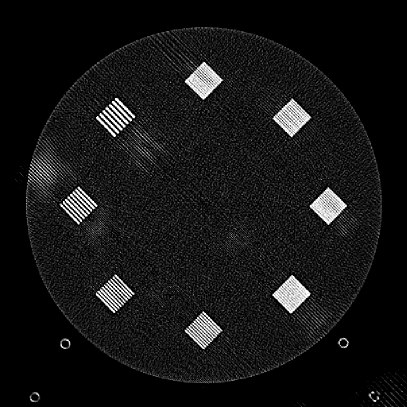

Figure 10: Clinical Standard hybrid IR vs JENG performance, with a display window center of 650 HU and a window width of 1500 HU. The spatial frequencies for bar patterns from top going clock-wise are 1.2, 1.0, 0.9, 0.8, 0.7, 0.6, 0.5, 0.4 mm-1. (a) The clinical Standard hybrid IR at L1 denoising strength using a soft tissue high contrast kernel. Note that significant aliasing streaking artifacts are present near the bar patterns. (b) JENG at a comparable L1 noise level but with much clearer bar pattern and fewer artifacts than the clinical standard hybrid IR. (c) The clinical standard hybrid IR at a stronger denoising strength of L3. (d) JENG at a comparable L3 noise level.

The first experiment we performed was a visual comparison of in-plane spatial resolution between JENG and the clinical standard hybrid IR. We used the ACR phantom module 4 for this evaluation, which has 8 resolution bars of various spatial frequencies from 0.4 mm-1 to 1.2 mm-1. To obtain a fair comparison, we matched the image noise variance in the uniform regions of JENG and the clinical standard hybrid IR and studied their in-plane spatial resolution and undersampling streaking artifacts. In addition, we performed two sets of experiments. The first set of experiments matched their image noise variance at the L1 denoising strength of the clinical standard method with a noise variance of 33926 in the uniform regions. The second set of experiments matched their image noise variance at stronger L3 denoising strength of the clinical standard method with a noise variance of 12988 in the uniform regions.

Fig. 10 is an example image for resolution bars and the spatial frequencies for the bar patterns from top going clockwise are 1.2, 1.0, 0.9, 0.8, 0.7, 0.6, 0.5 and 0.4 mm-1. Fig. 10(a) is the resolution bars reconstructed by the clinical standard hybrid IR at L1 denoising strength. Fig. 10(b) is JENG reconstructed at an image noise variance comparable to the L1 denoising. Fig. 10(c) is the clinical standard hybrid IR at a stronger L3 denoising strength and we can observe that the result at L3 denoising leads to less image noise than the result at L1 denoising in Fig. 10(a). Fig. 10(d) is JENG at an image noise variance comparable to the L3 denoising. To help readers better see the image quality difference between the clinical standard hybrid IR and JENG, Fig. 11 is the difference image between the two algorithms at L1 denoising. A noticeable difference between the clinical standard hybrid IR and JENG is that the clinical standard method in Figs. 10(a) and (c) have strong undersampling aliasing artifacts near the phantom periphery, which show a pattern of high density streakings and the streakings point along the direction of X-rays. In addition, the magnified sub-figures show that the bar pattern at 0.8 cycles/mm is unresolved with blurry details. In contrast, JENG in Figs. 10(b) and (d) effectively decimates the undersampling artifacts and the bar pattern in the magnified sub-figures of JENG is completely resolved with clearer details.

For the clinical standard hybrid IR, a possible cause for its loss of image resolution and the presence of aliasing artifacts in the image periphery can be explained by the Nyquist-Shannon sampling theorem. Nyquist-Shannon sampling theorem concludes that the discrete projection sampling rate for an application that requires Fourier Transform and data interpolation must be sufficiently high to avoid alias in the frequency domain and capture all the needed information in the continuous image domain. Given that the clinical standard hybrid IR involves Fourier Transform and data interpolation operations, the low projection sampling rate at a high helical pitch of 2.8 might lead to aliasing artifacts and a loss of spatial resolution for the clinical standard method. In contrast, JENG has no Fourier Transform or data interpolation operations and is completely based on linear algebra and acquisition physics modeling. Therefore, JENG is not limited by Shannon-Nyquist Theorem and its images are less susceptible to aliasing artifacts and show clearer bar patterns.